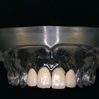

- プラタナス会独自のノウハウと技術を用いて、患者さん一人ひとりに合わせたものを医院内部の技工所で作製しています。治療内容は、セラミックの冠を被せる治療方法や、薄く歯の表面を削り、セラミックを貼り付けて白くする方法など、治療内容は要望に応じて多岐にわたります。

- セラミックの冠を被せることにより より自然な形態・色調に回復することができました。金属を使わないので歯肉のメラニン変色が起こりません。また、金属アレルギーの方も安心して治療を受けていただけます。